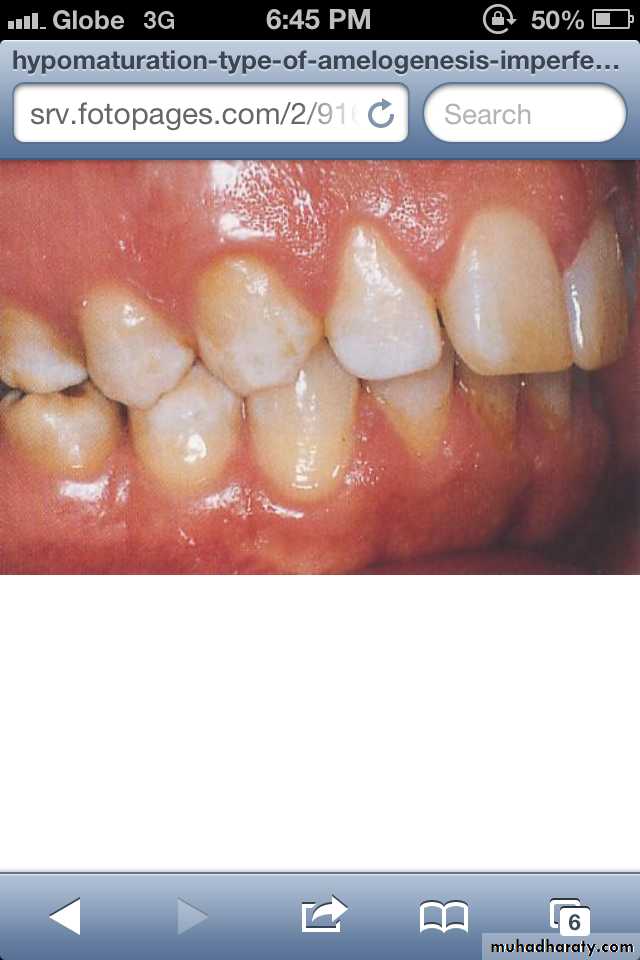

Hypomaturation Amelogenesis Imperfecta:

*Enamel is normal in form on eruption but:

opaque.

white to brownish-yellow.

softer than normal.

tends to chip from underlying dentin.

Radiographically:

Affected enamel exhibits radiodensity similar to dentin.